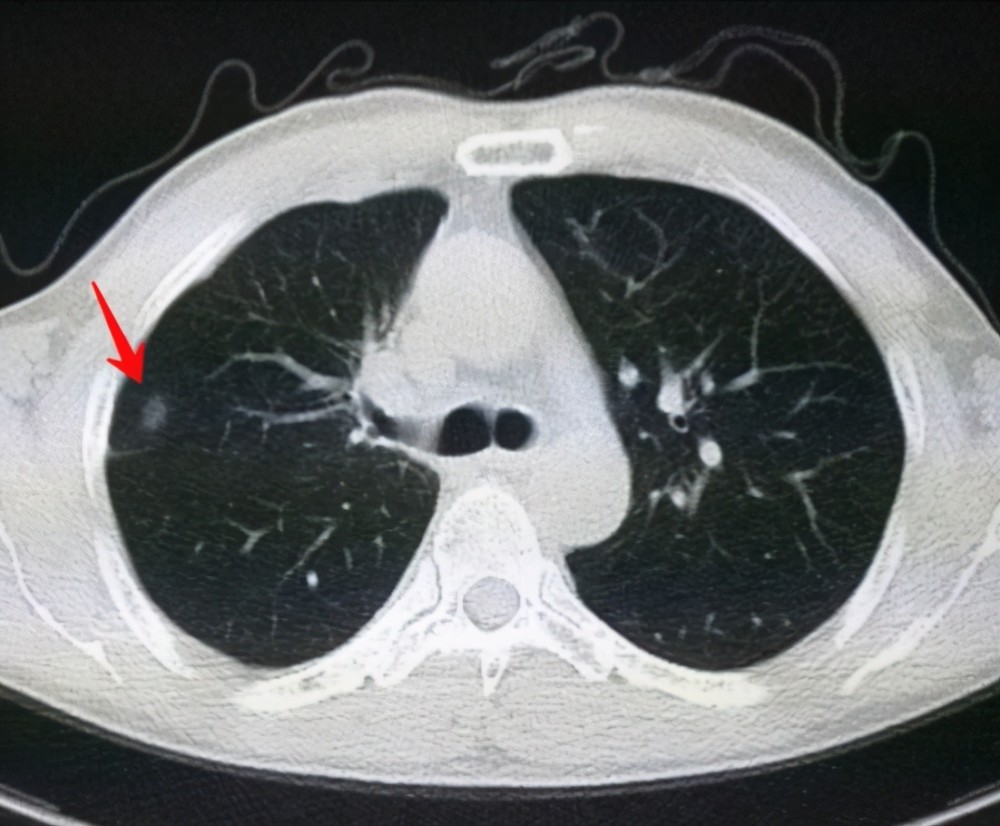

肺結(jié)節(jié)是一種常見(jiàn)的肺部疾病,其發(fā)病率逐年上升,雖然肺結(jié)節(jié)多數(shù)情況下是良性的,但也有可能惡化為肺癌,了解肺結(jié)節(jié)的形成原因?qū)τ陬A(yù)防和治療具有重要意義,本文將為您詳細(xì)解析肺結(jié)節(jié)的形成機(jī)制。

環(huán)境因素是肺結(jié)節(jié)形成的重要原因之一,長(zhǎng)期暴露于污染環(huán)境中,如空氣污染、化學(xué)污染等,可能導(dǎo)致肺部吸入有害物質(zhì),從而引發(fā)肺結(jié)節(jié),長(zhǎng)期接觸石棉、硅塵等職業(yè)環(huán)境因素也可能增加肺結(jié)節(jié)的發(fā)病風(fēng)險(xiǎn)。

6、定期體檢:定期進(jìn)行肺部檢查,及時(shí)發(fā)現(xiàn)并治療肺結(jié)節(jié)。